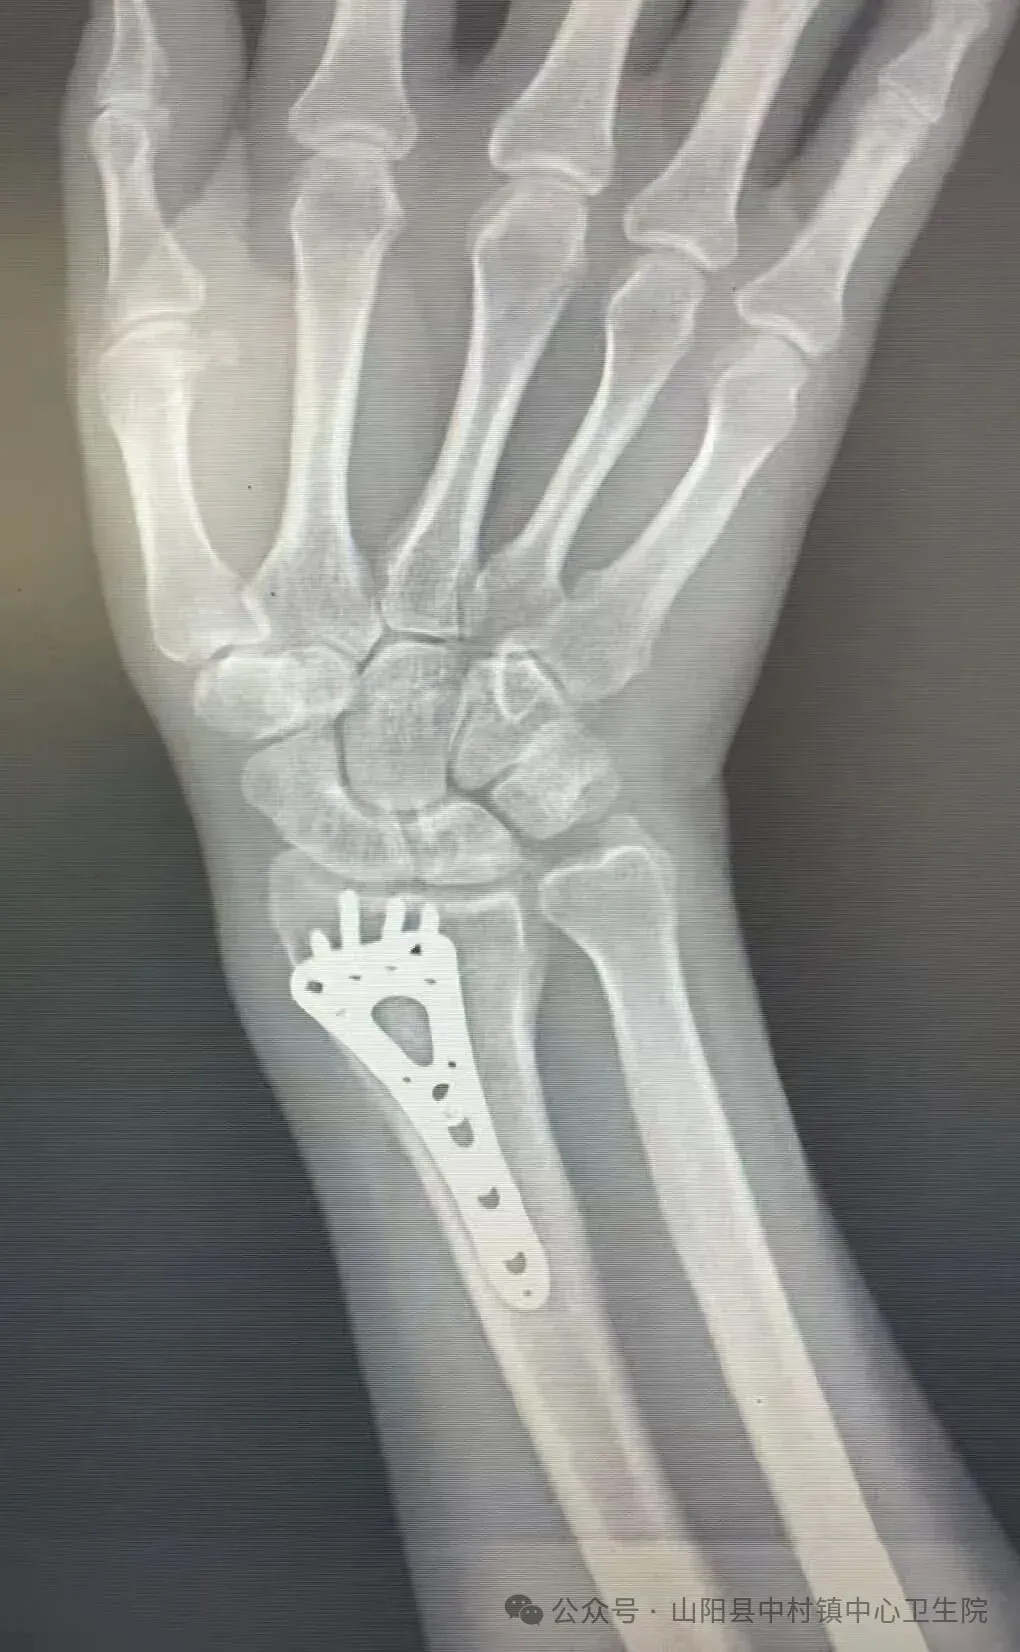

患者吴吉敏,男,47岁,以“右侧桡骨骨折术后1年”主诉于2026年01月28日09时42分入院。山阳县中村镇中心卫生院医疗副院长张立与两岭分院院长党世伟经过会诊评估后,确定了手术方案。手术由山阳县人民医院总院麻醉科主治医师陈新玲、手术室主管护师王盼、山阳县人民医院两岭分院院长党世伟、于2026年1月29日联合山阳县中村镇中心卫生院外科团队在臂丛麻醉下行右侧桡骨内固定物取出术,麻醉效果满意,手术过程顺利,患者生命体征平稳。